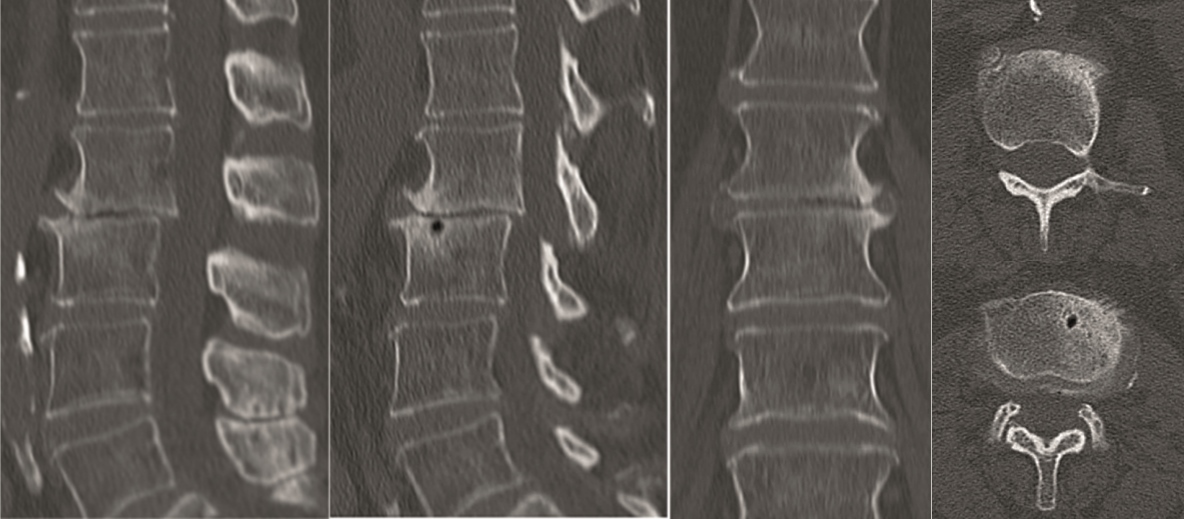

Multilevel facet pathology is shown in Fig 6. Intraoperative and postoperative images are shown (Fig 7-9).